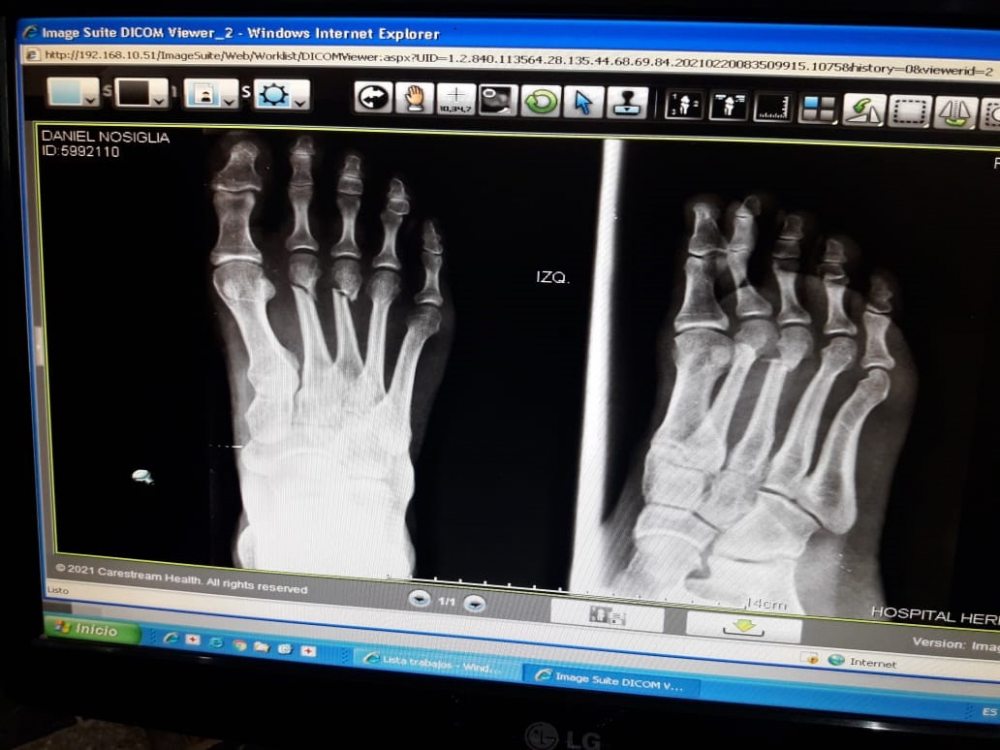

“Había transitado el km. 45 de la segunda etapa, no sufrió ninguna caída, fue una situación inexplicable. Su pie izquierdo tuvo un golpe fuerte con algún objeto fijo (raíz de árbol) que dejó como resultado dos fracturas en el 2° y 3° hueso Metatarsiano del pie izquierdo”, explicó el equipo del boliviano desde Argentina.